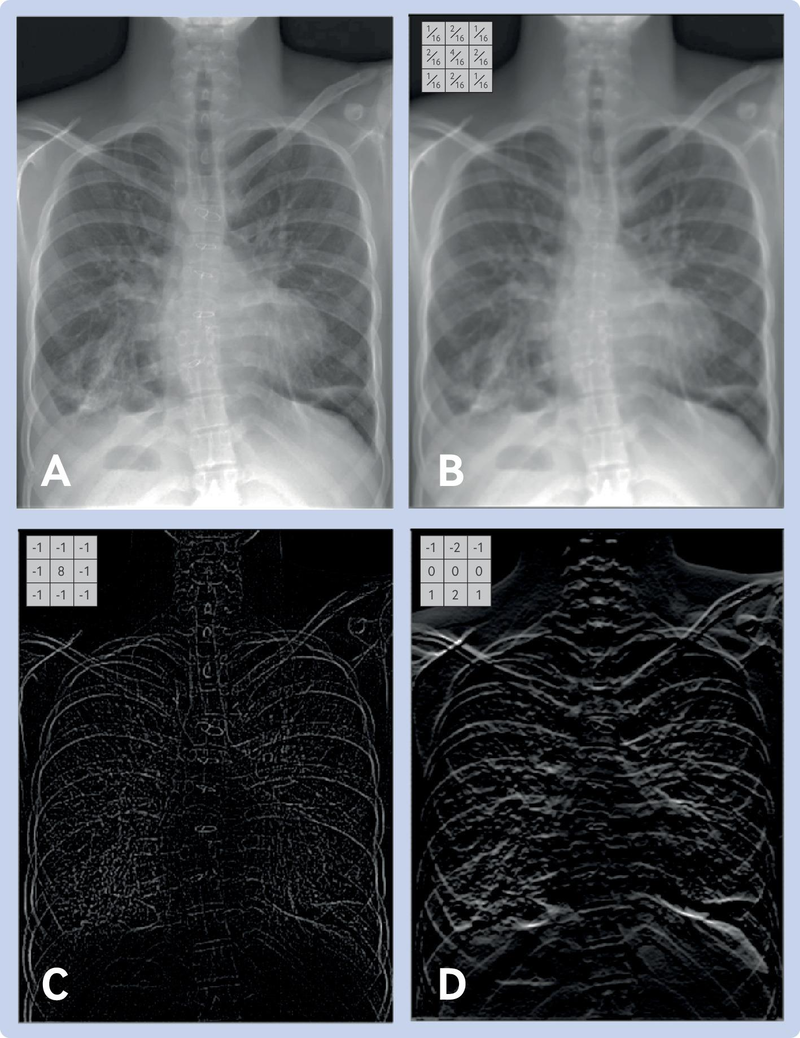

What is a Filter in a CNN?¶

A filter (also called a kernel) is a small matrix of weights that slides over the input image. At each position, it multiplies its weights with the underlying pixel values and sums them up to produce a single output value. This process is called convolution.

- Each filter is designed to detect a specific pattern, such as an edge, corner, or texture.

- In early layers, filters might detect simple features (like vertical or horizontal edges).

- In deeper layers, filters can detect more complex patterns (like shapes or objects).

Example:

A 3×3 filter moves across the image, looking for a specific pattern everywhere. The same filter (with the same weights) is used at every location—this is called parameter sharing.

B. Core CNN Components¶

- Convolutional Layer:

- Applies learnable filters across the input image

- Each filter detects specific patterns (edges, textures, etc.)

- Key parameters: filter size, number of filters, stride, padding